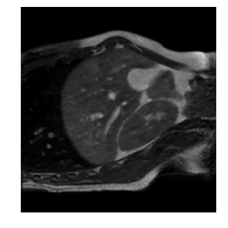

Qualitative results are shown in Fig. 4. We observe no large qualitative differences in the performances of MFIN and MFINc for either loss function. Since, MFINc-SSIM provides the best quantitative results, we show interpolated images from this method and compare them against SCIN-SSIM. Both methods perform well when the motion between the neighbouring images is low. This is reflected in the absence of any structures in the error images in Fig. 4.1. However, RMSE is lower for SCIN because it produces a denoised interpolated image, while MFIN carries over the noise pattern from the neighbouring known image. Whenever there exists high motion between the images being interpolated, SCIN produces blurry images and often misses image structures. This can be observed in cases 2-4 in Fig. 4. For all these cases, MFINc (and also MFIN) produces sharp images and largely preserves structures in the images. Fig. 4.2 shows a case where MFINc additionally has a much better performance with respect to image alignment. Fig. 4.3 shows a representative case, with small improvement in image alignment, yet worse RMSE and SSIM values for MFINc. Finally, Fig. 4.4 shows a case, where MFINc produces worse alignment of structures than SCIN.

1)

14.13, 0.81 13.02, 0.84

2)

9.16, 0.76 10.12, 0.74

3)

9.75, 0.85 12.94, 0.81

4)

a b c d e